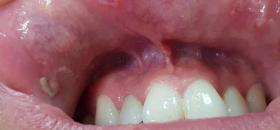

Проявления первичного сифилиса могут быть в области половых органов, слизистых рта, анального отверстия.

Иногда можно обнаружить ранки на губах, языке, миндалинах, веках или даже пальцах.

Как выглядит шанкр?

Внешне язвочка имеет округлую, ровную форму.

Границы образования четко очерчены и ровные как блюдце.

Размеры шанкра небольшие.

Сифилитический шанкр можно определить по характерному оттенку, который имеет ярко-красную окраску.

Сверху шанкр имеет блестящую поверхность, с которой выделяется серозное вещество в небольших количествах.

Амигдалит – это клиническая форма заболевания, которая характеризуется увеличением миндалины.

Можно увидеть покраснение слизистых оболочек, которые сопровождаются болезненными ощущениями.

В некоторых случаях клиническую картину можно перепутать с таким заболеванием, как ангина.

Можно обнаружить на коже или часто на слизистых ротовой полости.

Папулезные сифилиды имеют способность сливаться в одну большую бляшку.

Ротовая полость может поражаться сифилисом на любом этапе развития заболевания: атипичное расположение первичного сифилида, обширные высыпания во вторичную фазу и вегетации в третичном периоде.